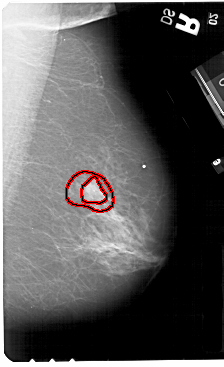

A_1574_1.RIGHT_CC

FILE: A_1574_1.RIGHT_CC.OVERLAY

TOTAL_ABNORMALITIES 1

ABNORMALITY 1

LESION_TYPE MASS SHAPE IRREGULAR MARGINS ILL_DEFINED

ASSESSMENT 5

SUBTLETY 5

PATHOLOGY MALIGNANT

TOTAL_OUTLINES 2

BOUNDARY

CORE